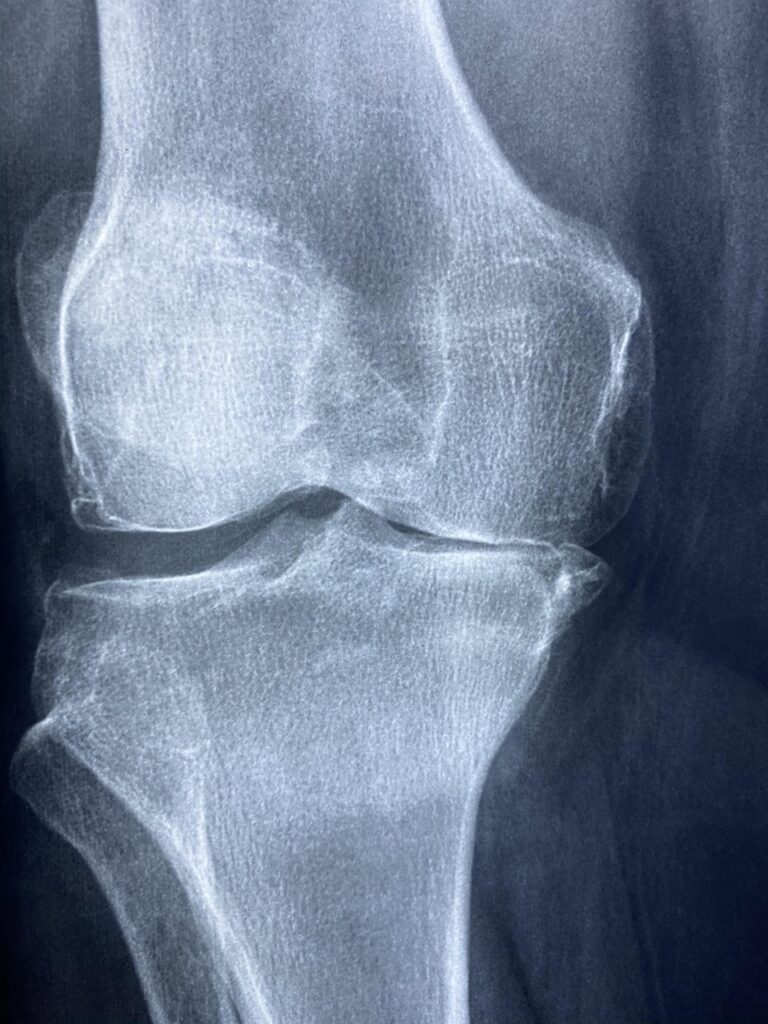

膝蓋軟骨軟化症の診断は、医師による問診や身体検査、X線検査やMRIなどの画像診断を通じて行われます。これにより、軟骨の状態や膝関節の構造に異常がないかを確認します。